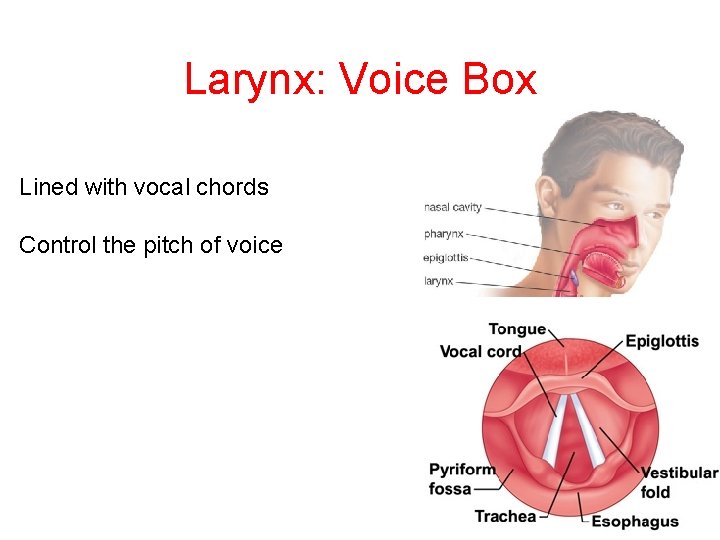

Larynx: Voice Box Lined with vocal chords Control the pitch of voice